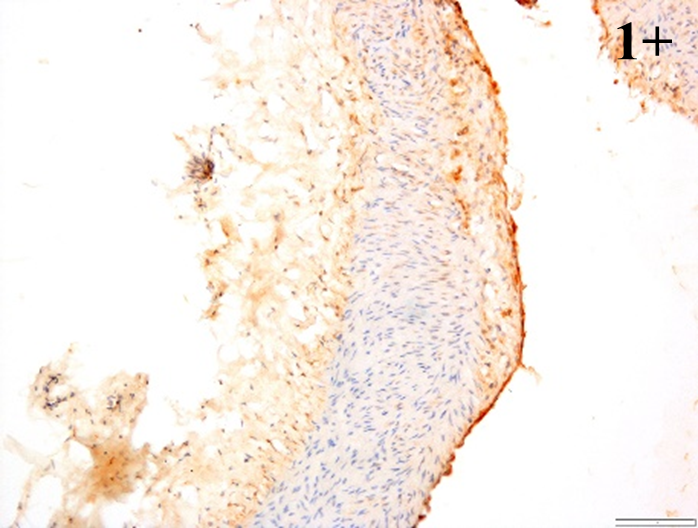

According to the percentage endothelial staining of cells, semi-quantitative

scores were applied. Score: 0 (negative); 1+ (1–10% positive cells); 2+

(11–25% positive cells) and 3+ (